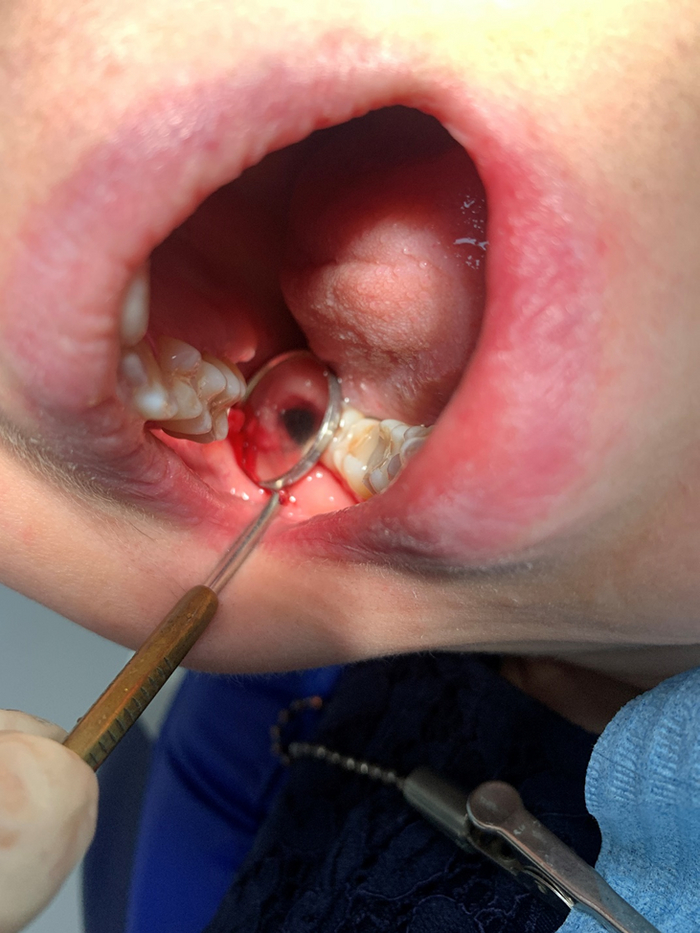

Вот слюноотсос с наконечником

Вот дырка в зеркале

Далее мы, положив пациента горизонтально, чтобы корень упал на заднюю стенку пазухи, мы пихаем наконечник работающего слюноотноса в пазуху через эту дырку и шерудим там им. Работаем медленно и аккуратно. Иногда просим пациента потрясти головой, если вдруг корень прилипнет где-то на другой стенке. И самое главное прислушиваемся к звуку. Обычно слюноотсос звучит так: «Ф-Ф-Ф-Ф-Ф-Ф-Ф-Ф-Ф-Ф-Ф-Ф-Ф». Как только мы услышем, что он начал захлебываться и по его трубке что-то застучало, либо если звук сменился на глухое «Х-Х-Х-Х-Х-Х-Х-Х-Х-Х-Х-Х», то медленно и аккуратно достаем его из пазухи. Если корешок маленький, то он засасывается в слюноотсос, а большой тупо присасывает к наконечнику и вытянем наружу.